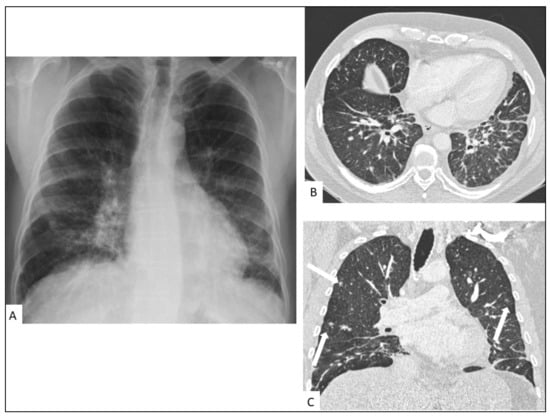

5.1. Pulmonary KS